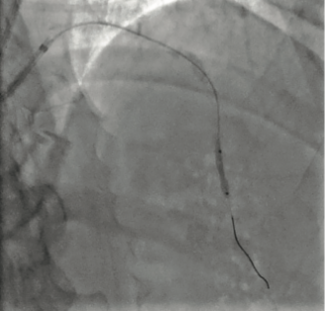

An 80-year-old man with a history of acute inferior myocardial infarction was admitted to our hospital. He had undergone bare-metal stent (3.5/28 mm) implantation in the mid-right coronary artery 22 years prior.